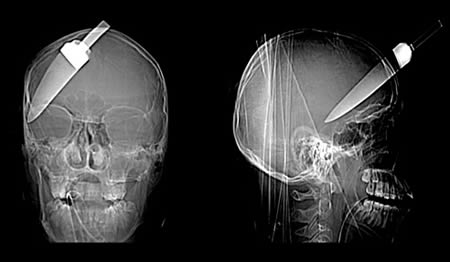

این عکس نشون میده که این پسر بچه از یک حادثه کشنده جون سالم به در برده و با اینکه یک چاقوی 5 اینچی وارد سرش شده ولی زنده مونده.این پسربچه 16 ساله به همراه دوستاش تو ایستگاه اتوبوسی در لندن در سال 2008 دعواشون میشه و این بلا سرش میاد.